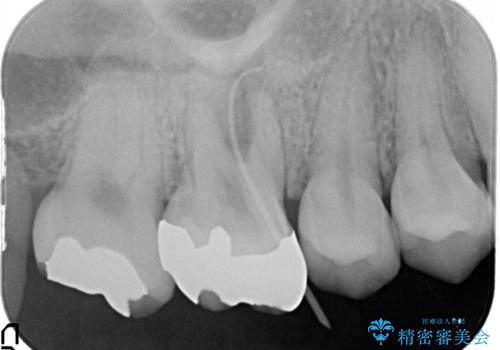

- 右上の歯茎が腫れてきたとのことで来院されました。

右上6番目の歯の位置に腫脹があり、膿も出ている状態でした。

レントゲンを撮影すると、根の先端から膿が排出されていることがわかりました。

根の神経の治療を行い、セラミックを装着する計画としました。